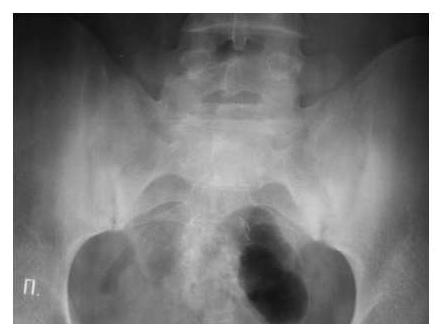

Рис. 7. Двусторонний сакроилиит у больного серонегативным спондилоартритом.

Околосуставной остеопороз в отличие от РА выявляется только в острую стадию артрита. Одна из основных локализаций, где развиваются костные пролиферации - это краевые отделы крестца и подвздошных костей (рис. 7).